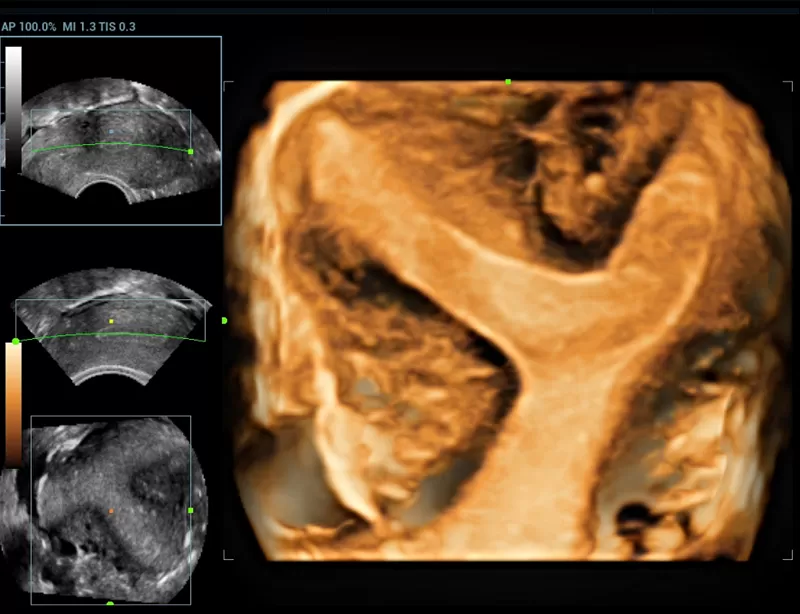

Στη διάθεση σας θα βρίσκονται καταρτισμένοι συνεργάτες μας οι οποίοι θα αναλάβουν να σας παρουσιάσουν τις δυνατότητες του Premium υπερηχογράφου Resona που αποτελεί μια πραγματικά επαναστατική πλατφόρμα, με δεκαπλάσια ταχύτητα σάρωσης χάρις στη μοναδική τεχνολογία zone sonography technology ZST+ που διαθέτει.

Η σειρά Resona ξεχωρίζει όχι μόνο για την κορυφαία απεικονιστική της τεχνολογία αλλά και για τα ευέλικτα εργαλεία ανάλυσης, προσφέροντας ποιότητα απεικόνισης υψηλού επιπέδου και αυξημένη διαγνωστική ακρίβεια.

Οι καινοτόμες τεχνολογίες:

- New iLive with Hyaline

- Smart Face

- Dynamic Focusing

- HD Scope

καθιστούν τη σειρά Resona μια από τις πιο ισχυρές διαγνωστικές πλατφόρμες που υπάρχουν σήμερα στην υπηρεσία της Ιατρικής.